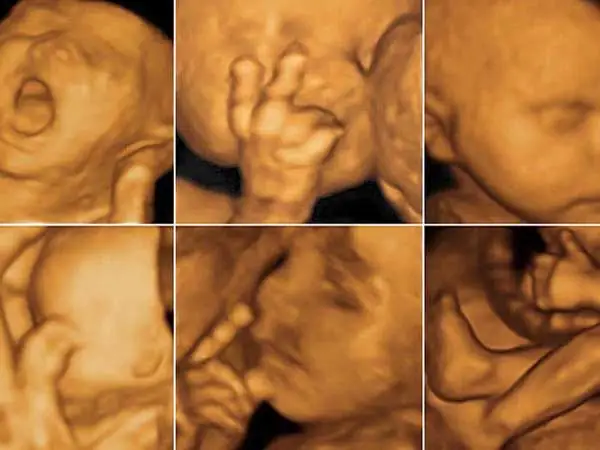

Tuần 21 đánh dấu một cột mốc phát triển quan trọng. Lúc này, thai nhi đã lớn hơn, các cơ quan nội tạng đã hình thành đầy đủ và hoạt động, đồng thời lượng nước ối dồi dào giúp hình ảnh siêu âm trở nên rõ nét hơn bao giờ hết. Siêu âm 4D không chỉ cho mẹ chiêm ngưỡng khuôn mặt, nụ cười hay cử động đạp chân của con mà còn là công cụ y khoa thiết yếu để:

- Siêu âm 4D: Là hình ảnh 3D động, có thêm yếu tố thời gian. Mẹ có thể thấy con chuyển động, chớp mắt, mút tay, hay thậm chí là “cười” trong bụng.